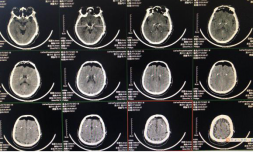

9月6日,我院神经外科梁建荣主任团队完成我市首例帕金森病DBS手术治疗,也是全省第三家开展此项技术单位,标志着我院神经外科功能神经外科组取得技术新突破。此项技术的开展,包括患者术前的评估、高清晰3.0T核磁3D成像技术、64排CT薄层扫描及图像融合技术等,得到我院神经内科、手术室、麻醉科、核磁室、CT室及职能科室的大力支持,充分体现了我院MDT多学科合作。项目的开展得到首都医科大学附属天坛医院功能神经外科张建国主任、山西省人民医院神经外科功能组马久红主任的技术支持。

患者男性,60岁,患有帕金森病12年余,口服药物治疗欠佳,症状持续加重使其无法起床站立、行走,语言能力下降,无法握笔书写,患者深感痛苦,家属也束手无策,来我院神经外科就诊,经过认真评估后决定由我科为期实施DBS手术治疗。术前经过充分评估、制定周密手术计划,与患者及家属充分沟通后于2020年9月6日上午实施DBS手术治疗。

术中患者神志保持清楚,植入电极至靶点后,立即测试四肢肌张力及运动功能,术前症状即已明显改善。